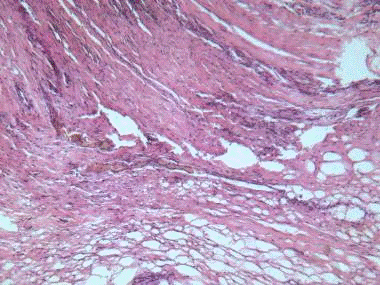

) Технические причины: не берется первичный очаг (см. приложение

1); пограничная зона, где много нормальной ткани (см. приложение 2); участок с

низким процентным содержанием опухолевой ткани в биопсии (см. приложение 3);

остатки биопсии, где мало опухолевой ткани (см. приложение 4);

) Морфологическое строение опухоли: много слизи, мало раковых

клеток (см. приложение 5); прорастание соседних тканей и метастазы (островки

раковых клеток среди других тканей - соединительной, мышечной или брюшине) (см.

приложения 6,7);